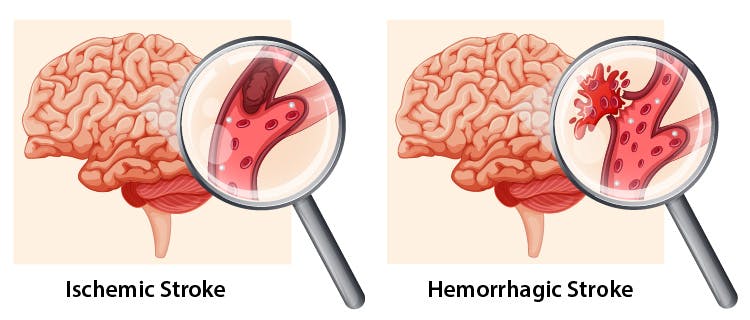

Có 2 loại đột quỵ là đột quỵ do thiếu máu và đột quỵ do xuất huyết

Trong đột quỵ xuất huyết não, máu chảy trực tiếp vào nhu mô não. Cơ chế thường là rò rỉ từ các động mạch nội sọ nhỏ bị tổn thương do tăng huyết áp mãn tính.

Đột quỵ xuất huyết não ít phổ biến hơn đột quỵ do thiếu máu não. Các thống kê dịch tễ học cho biết chỉ có 8-18% đột quỵ là xuất huyết . Tuy nhiên, đột quỵ xuất huyết có tỷ lệ tử vong cao hơn đột quỵ do thiếu máu não Ngoài ra, người bệnh có thể gặp phải cơn thiếu máu não thoáng qua. Đây là tình trạng đột quỵ nhỏ, dòng máu cung cấp cho não bộ bị giảm tạm thời. Người bệnh có những triệu chứng của đột quỵ nhưng chỉ diễn ra trong thời gian rất ngắn, thường kéo dài khoảng vài phút. Đây là dấu hiệu cảnh báo nguy cơ đột quỵ có thể xảy ra bất cứ lúc nào mà người bệnh cần lưu ý.

- Đột quỵ do thiếu máu cục bộ: Chiếm khoảng 85% tổng số các ca bị đột quỵ hiện nay. Đây là tình trạng đột quỵ do các cục máu đông làm tắc nghẽn động mạch, cản trở quá trình máu lưu thông lên não.

- Đột quỵ do xuất huyết: Đột quỵ do xuất huyết là tình trạng mạch máu đến não bị vỡ khiến máu chảy ồ ạt gây xuất huyết não. Nguyên nhân khiến mạch máu vỡ là do thành động mạch mỏng yếu hoặc xuất hiện các vết nứt, rò rỉ.